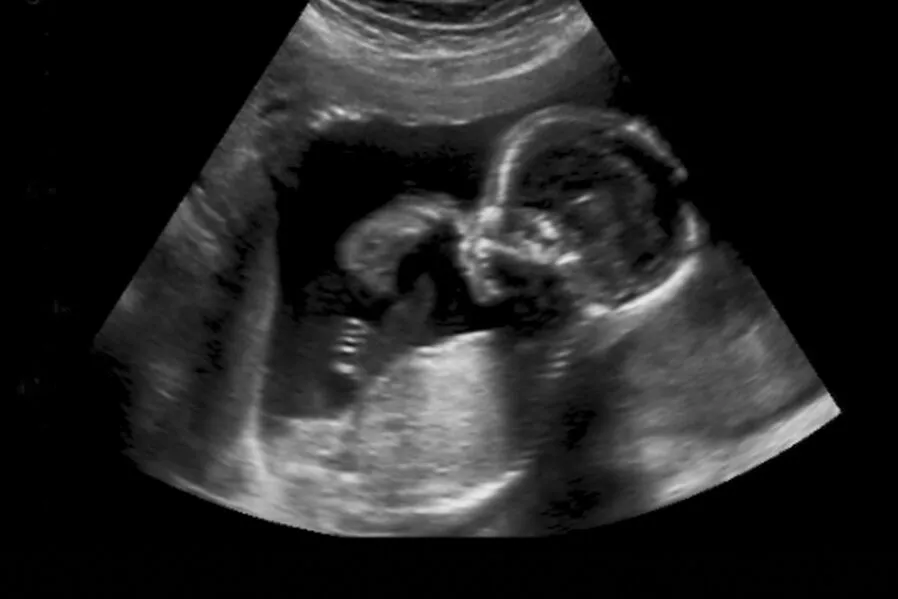

Ultraschall in der Schwangerschaft: Wichtige Termine und Zusatzleistungen

Ultraschalluntersuchungen spielen in der Schwangerschaftsvorsorge eine zentrale Rolle. Sie ermöglichen es, die Entwicklung des Kindes zu verfolgen, mögliche Komplikationen frühzeitig zu erkennen und werdenden Eltern einen Blick auf ihr Baby zu ermöglichen.

Im Rahmen der gesetzlichen Schwangerschaftsvorsorge sind drei umfassende Ultraschalluntersuchungen vorgesehen, die von den Krankenkassen übernommen werden:

- Der erste große Ultraschall findet meist um die 10. Schwangerschaftswoche statt und dient der Überprüfung der Fruchtwassermenge, der Größe und Entwicklung des Embryos sowie der Bestätigung der Schwangerschaft.

- Der zweite große Ultraschall wird um die 20. Schwangerschaftswoche durchgeführt. Hierbei wird eine detaillierte Untersuchung der Organe des Kindes vorgenommen, um Fehlbildungen auszuschließen.

- Der dritte große Ultraschall erfolgt um die 30. Schwangerschaftswoche und konzentriert sich auf das Wachstum des Kindes, seine Lage im Mutterleib und die Beurteilung der Plazenta und des Fruchtwassers.

Darüber hinaus gibt es spezialisierte Ultraschallverfahren wie den 3D- oder 4D-Ultraschall, die besonders detailreiche und lebensechte Bilder des Kindes liefern, sowie die Doppler-Sonographie zur Untersuchung der Durchblutung. Diese werden in der Regel als Wunschleistungen (IGeL) angeboten, wenn keine medizinische Notwendigkeit für ihre Durchführung besteht.